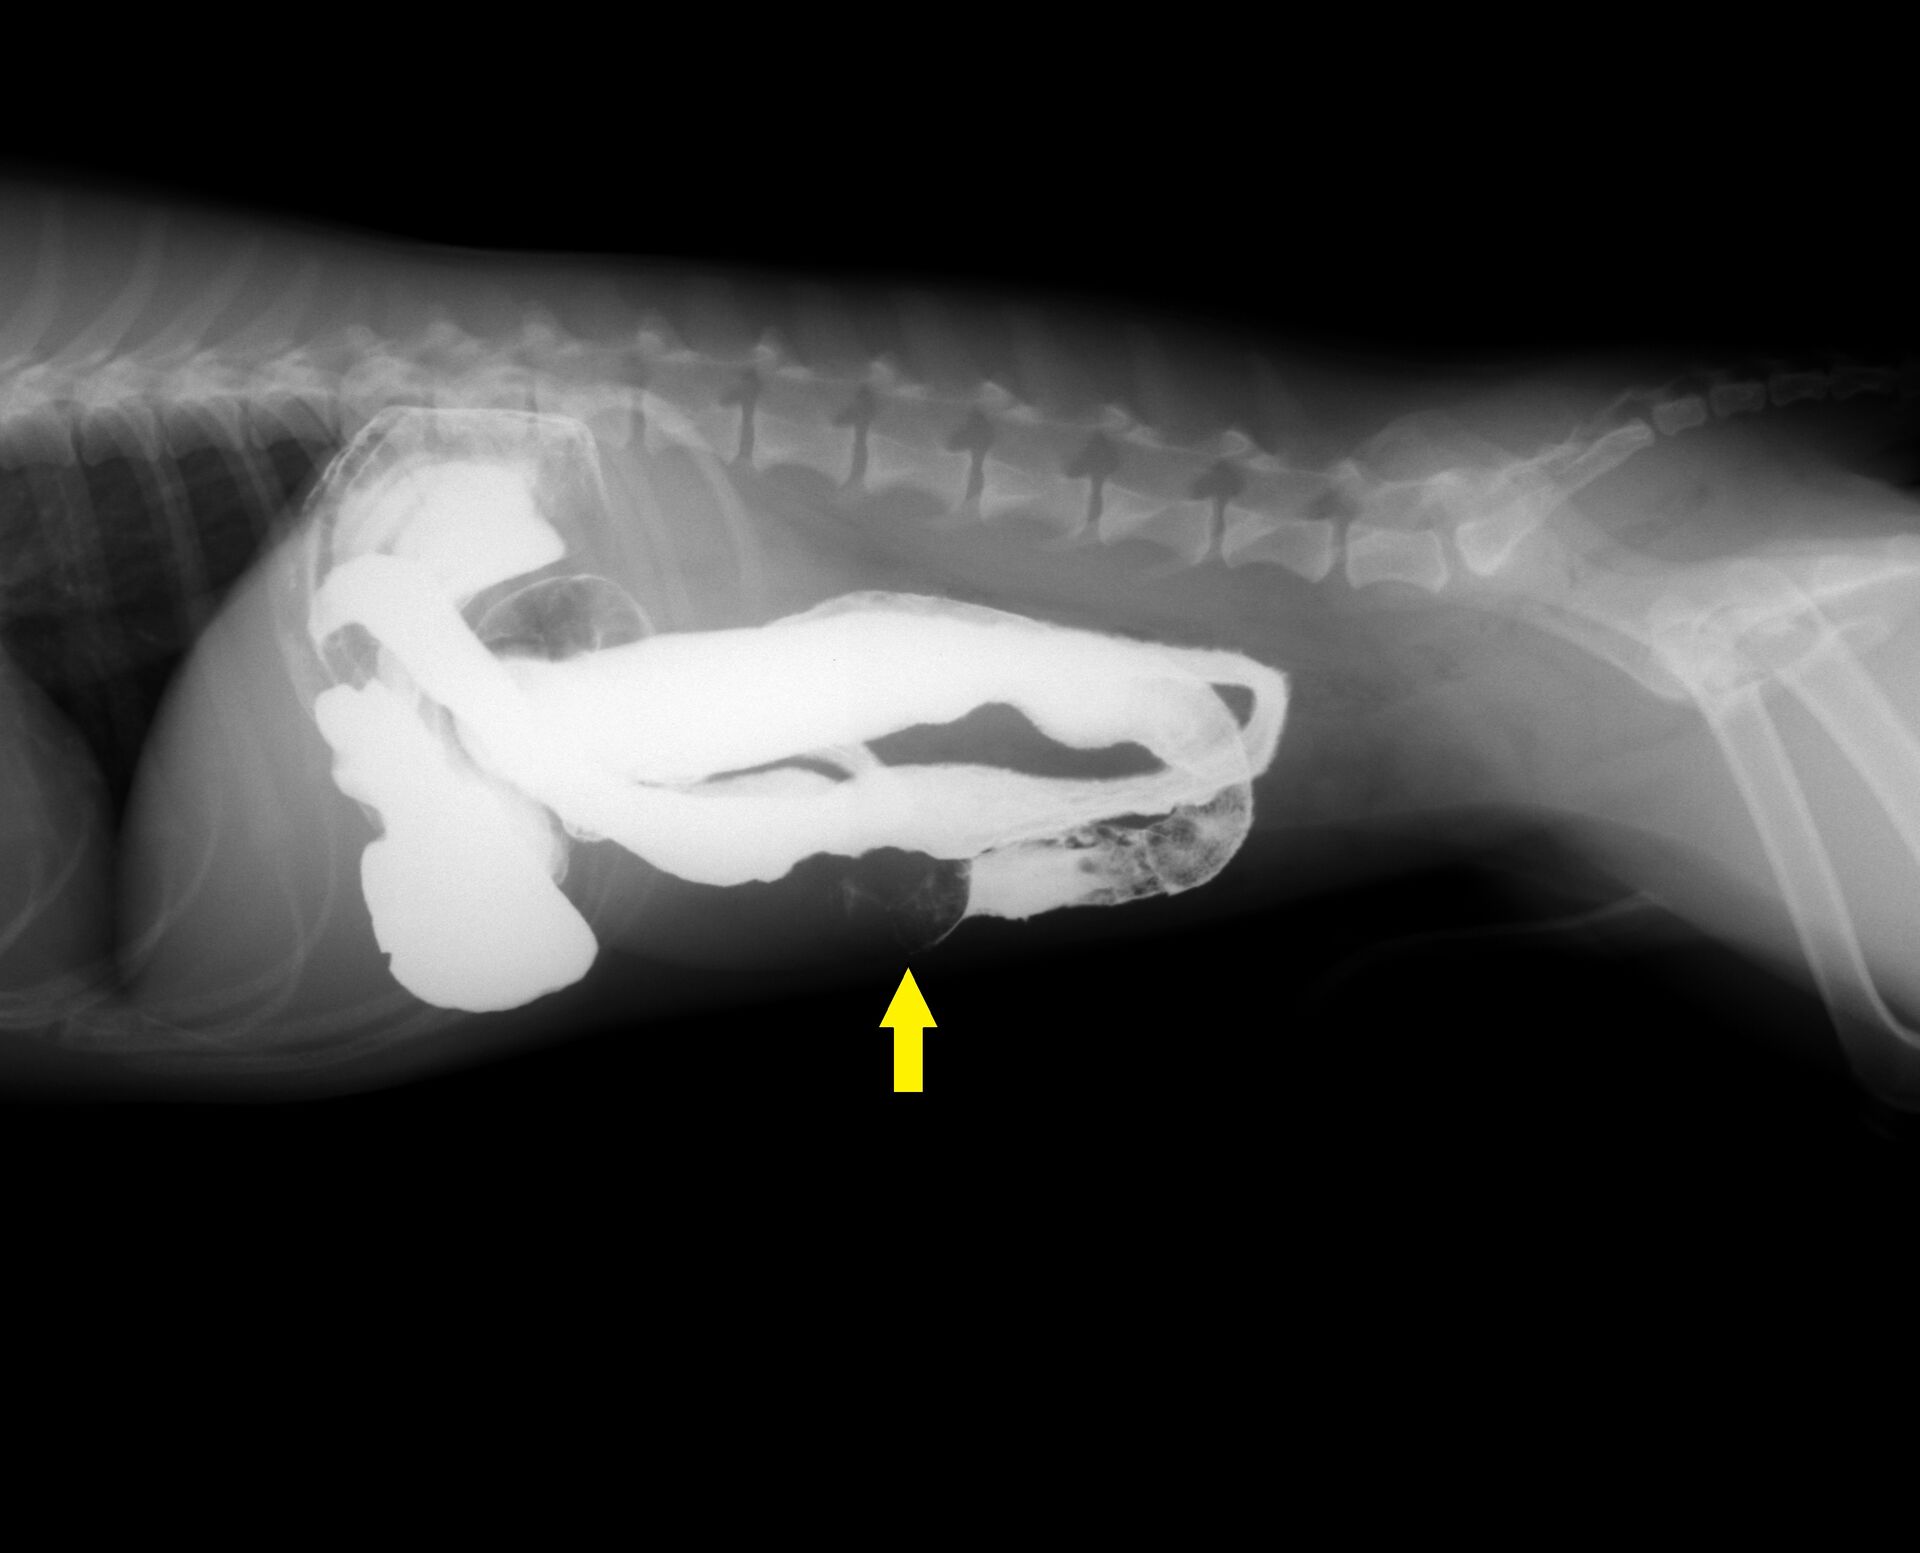

胃から十二指腸にかけて普通より少しガスが多く認められました。益々異物による腸閉塞が疑われたので、バリウム検査を行うことにしました。その結果が以下です。

バリウム投与後15分です。

バリウム投与後30分です。

黄色矢印のところでバリウムが止まって円形の異物のようなものが認められました。その後もバリウム投与後2時間までレントゲンを撮影しましたが、矢印のところからは全く進みませんでした。異物によって腸閉塞していることは疑いがありませんでしたので、手術を行いました。下の写真のように小腸内に異物が認められ、腸を切開し、異物を取り除きました。飼い主さんにお見せしたところ、いつも遊んでいるおもちゃの突起物であることがわかりました。